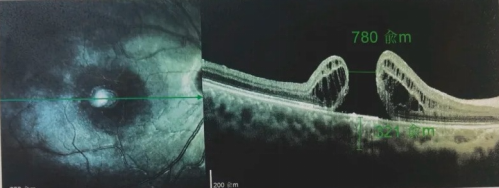

由于自身患有頸椎病,每次術(shù)后長期的趴睡都讓他痛苦不堪。為了尋求更好的治療,吳爺爺來到廈門大學附屬廈門眼科中心,找到了眼外傷及眼底病2科的李海波博士后。此時,吳爺爺右眼的黃斑裂孔已經(jīng)持續(xù)擴大到780μm,演變?yōu)殡y治性的大裂孔。

最讓吳爺爺難以置信的是:術(shù)后只需保持平躺24小時!第二天復查時,眼底鏡及OCT檢查清晰顯示——那個折磨了他大半年的大裂孔,竟然閉合了!且吳爺爺?shù)挠已垡暳τ辛嗣黠@的改善,術(shù)后3天已經(jīng)可以看到 0.15。